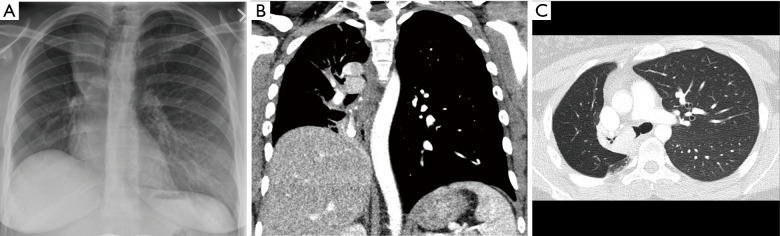

恶性中央气道阻塞(MCAO)影响着许多晚期原发性肺癌和胸腔转移性疾病患者,并可能导致患者出现严重症状和功能受限。由于症状通常不具有特异性,因此诊断可能具有挑战性,但随着怀疑程度的提高和新的胸部成像模式的出现,诊断率有所提高。支气管镜检查在 MCAO 的诊断和管理中起着至关重要的作用,治疗干预可能会挽救生命并缓解症状。这可能最终改善患者接受其他系统或局部癌症疗法或潜在肿瘤切除术的可能性。在病情初步稳定后,MCAO 患者必须及时接受评估和治疗。根据肿瘤特征、阻塞位置和远端气道的可行性,可使用多种支气管镜器械进行治疗,并可在治疗过程中结合使用。这些方式包括扩张、支气管内支架置入、热消融和非热消融、机械清创和新型支气管内治疗。虽然这些手术并非没有风险,但有大量证据显示,治疗性支气管镜手术后患者的症状、生活质量和存活率都有所改善。这篇综述文章概述了 MCAO 的诊断和治疗,重点是支气管镜干预。

Malignant central airway obstruction (MCAO) impacts many patients with advanced primary lung cancers and metastatic disease to the thorax and may cause substantial symptoms and functional limitations in those affected. Making the diagnosis may be challenging as symptoms are often non-specific but identification is improved with a heightened level of suspicion and newer thoracic imaging modalities. Bronchoscopy plays a crucial role in the diagnosis and management of MCAO and therapeutic interventions may be lifesaving and result in palliation of symptoms. This may ultimately improve a patient's candidacy to receive additional systemic or local cancer therapies or potential tumor resection. After initial stabilization, it is important that patients with MCAO undergo prompt evaluation and treatment. Multiple bronchoscopic instruments are available for management depending on tumor characteristics, location of the obstruction, and viability of distal airways, and may be utilized in combination during therapeutic procedures. These modalities include dilation, endobronchial stent placement, thermal and non-thermal ablation, mechanical debulking, and novel endobronchial therapies. While these procedures are not without risk, there is ample evidence showing improvements in patient symptoms, quality of life, and survival following therapeutic bronchoscopy. This review article provides a general overview of the diagnosis and management of MCAO with a focus on bronchoscopic interventions.